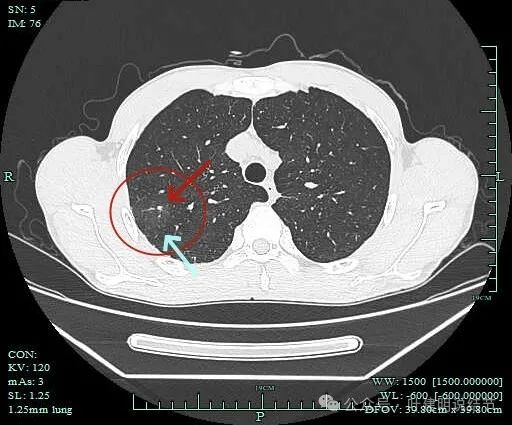

病灶2:

病灶出现,密度杂乱。

有磨玻璃成分,且轮廓清,磨玻璃边缘有细毛刺征,实性成分的边缘毛糙不平,形态不规则。

灶内有僵硬支气管走行,边上少许磨玻璃成分,病灶有一定收缩力。

灶内支气管穿行且显得僵硬。

胸膜牵拉,灶内支气管通气征并显僵硬,部分边缘有毛刺征。

有血管进入并异常增粗;病灶有分叶征,有毛刺征,也有胸膜牵拉征。

病灶有细毛刺征,感觉有收缩力。

实性成分为主,边上少许磨玻璃成分。

叶间胸膜牵拉。

这个病灶是非常典型的恶性的,总体上基本上是实性成分,但边上仍有少许磨玻璃,而磨玻璃成分有分叶与细毛刺,病灶内部有支气管通气征,且支气管显僵硬,又有异常增粗的血管进入。再加上胸膜牵拉、叶间裂牵拉,整体轮廓较清,周围肺野清爽,没有卫星灶。所以基本上就是浸润性癌了的。

上图是2023年1月时的,虽也基本上实性,但明显病灶相对较小,而且膨胀感不太明显些。

到2023年9月病灶较前进展,或许测量大小变化不明显,但实性成分明显多起来,内部不太致密的部分明显显得较之前密了。

到了2024年5月,病灶整体给人感觉有收缩力了些,内部也更显致密了。